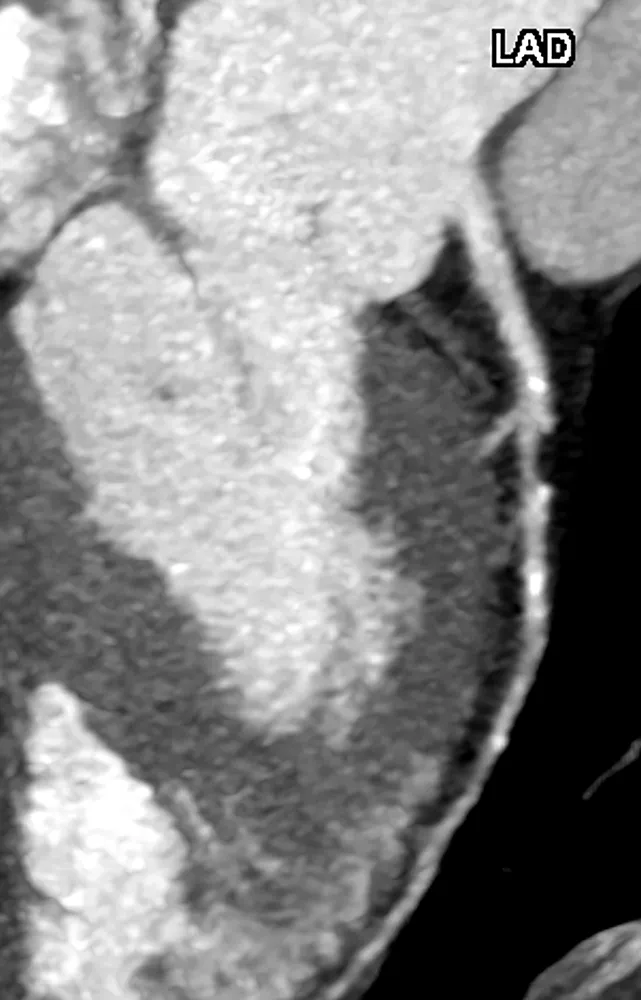

Die Koronar-CT-Angiographie (CCTA) hat sich als zentrales Verfahren in der präventiven Herz-Kreislauf-Medizin etabliert. Sie erlaubt die direkte, nicht invasive Darstellung der koronaren Anatomie, einschließlich der Plaquemorphologie und des Stenosegrads. Bereits im subklinischen Stadium lassen sich damit atherosklerotische Veränderungen erfassen, die bei konventioneller Diagnostik unentdeckt bleiben.

Zahlreiche Studien, darunter die SCOT-HEART-Studie, haben gezeigt, dass die Einbindung der CCTA zu einer verbesserten Ereignisvorhersage und gezielteren Therapieeinleitung führen kann [2]. Neben der Quantifizierung des Kalziumscores (Agatston) ermöglicht die CCTA auch die Beurteilung nicht kalzifizierter und gemischter Plaques. Besonders relevant sind morphologische Merkmale, wie low attenuation plaques, positives Remodeling, spotty calcifications und das „napkin-ring sign“, da sie mit instabilen, rupturgefährdeten Läsionen assoziiert sind (Abb. 2).

Die Beurteilung des Stenosegrads erfolgt auf Grundlage der luminalen Einengung. Eine Stenose > 50 % wird als potenziell hämodynamisch relevant eingeschätzt. Zur Beurteilung der funktionellen Relevanz kann bei Bedarf eine CT-basierte Bestimmung der fractional flow reserve (FFR-CT) oder eine weiterführende Ischämiediagnostik erfolgen (Abb. 3).

Insbesondere bei asymptomatischen Personen mit intermediärem Risiko bietet die CCTA somit einen präzisen Zugang zur Früherkennung klinisch stiller Atherosklerose. Die ESC-Leitlinien unterstützen ihren Einsatz ausdrücklich, sofern das Ergebnis Einfluss auf das therapeutische Vorgehen hat [3].